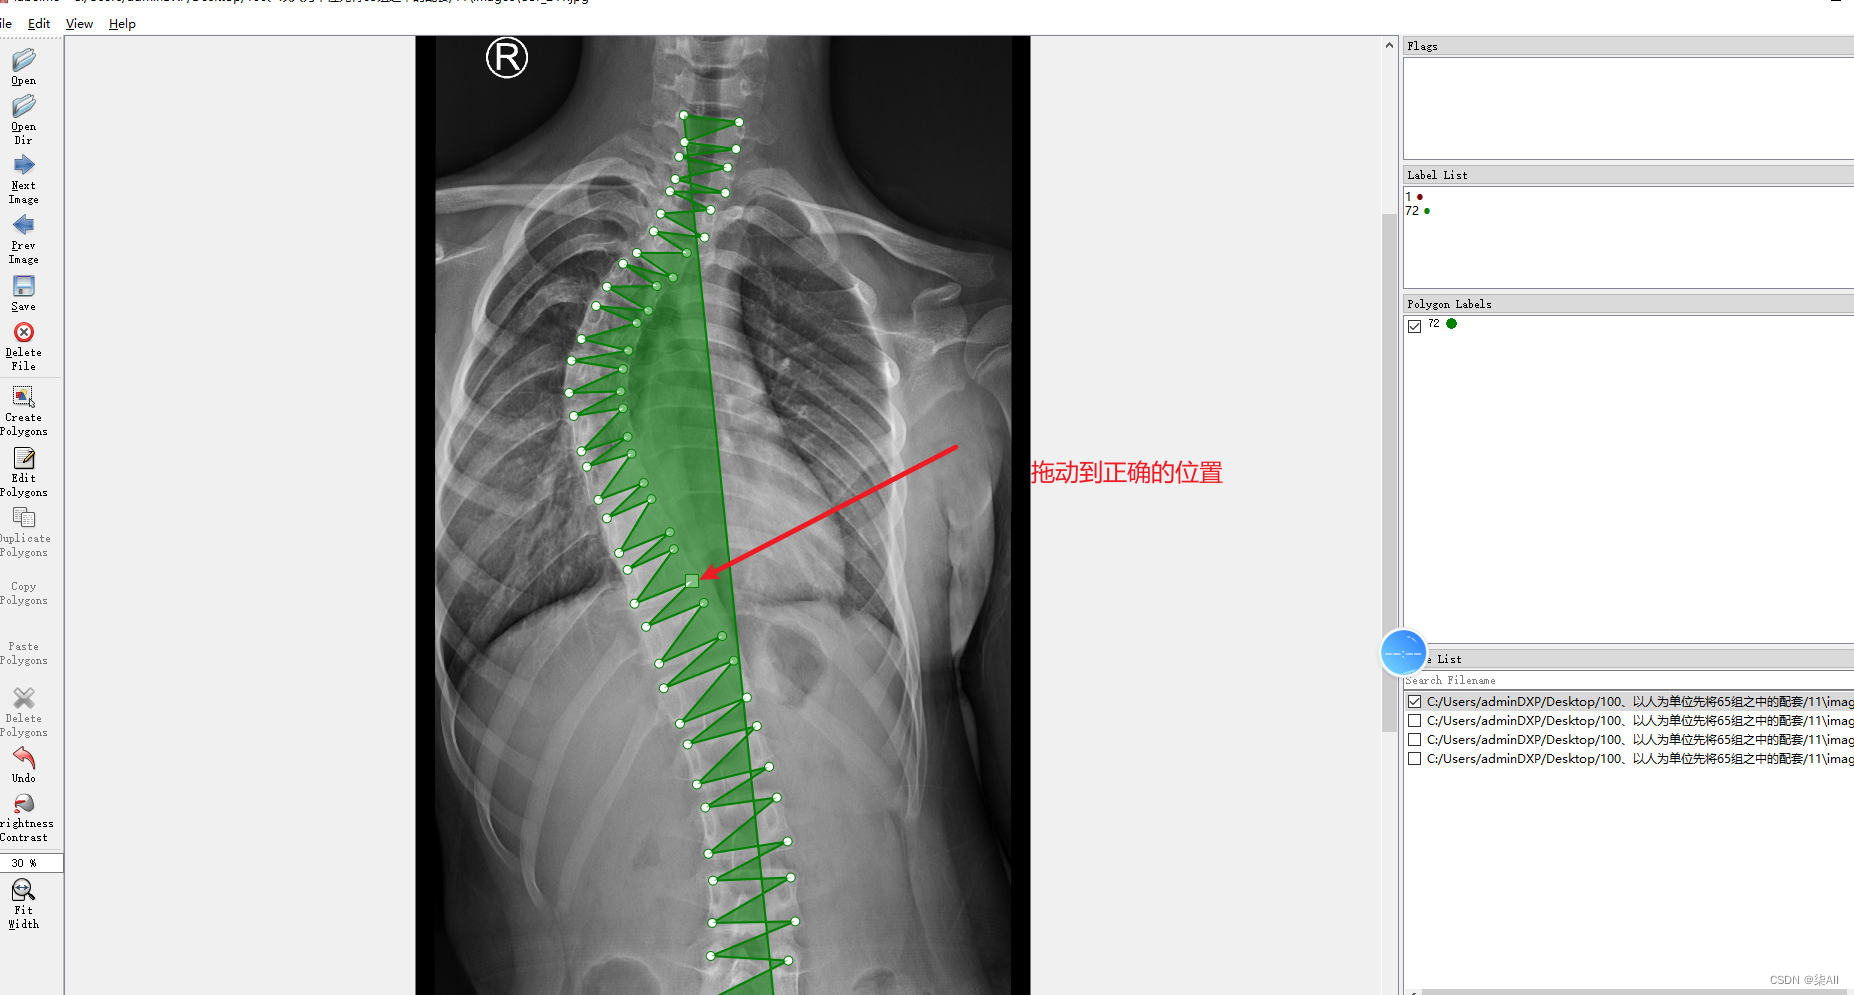

4、标注过程注意事项

4.1、关键点不小心标注的位置不对

4.2 少标记或者多标记点。进行补点或者进行删除